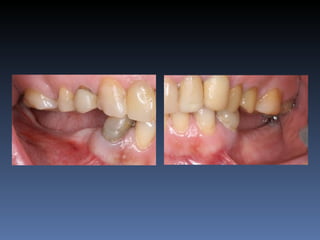

BOX 4

Eusébio Moreno

Idade – 73 anos

Sexo – Masculino

Raça – Caucasiana

ASA – II

Data- 23-04-2012

Diagnóstico: Desdentado parcial

bilateral posterior da maxila.

Plano de tratamento: Reabilitação posterior maxilar

esquerda, com instalação de 3 implantes endo-ósseos

(2.4,.2.5.2.6.), para reabilitação protética fixa.